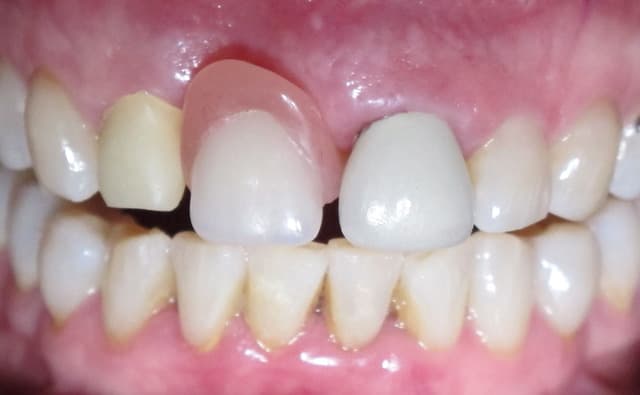

Img 5804 rvn38o - Eugenol

Img 5813 bhh1tm - Eugenol

Img 5820 kowclt - Eugenol

Img 5815 gymgib - Eugenol

Img 5816 okgijh - Eugenol